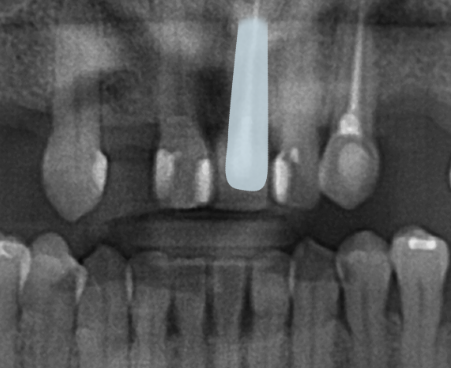

그럼, 식립한 사진을 함께 볼까요?

🔽

임플란트는 바로

치아 머리가 올라가는 게 아닌

골유착을 유도하기 위해

뿌리만 식립하고 3개월 정도

기다린 뒤

뼈와 임플란트가 잘 붙었는지

기계로 측정 후

잘 붙었다고 판단되면

본을 떠서 보철을 올려드리고 있어요.^^